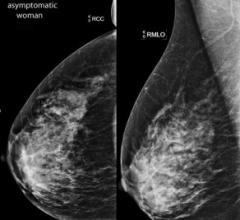

The fifth edition of Breast Imaging-Reporting and Data System (BI-RADS) Atlas issued by the American College of Radiology (ACR) included changes in breast density reporting categories. Volpara Solutions, producers of VolparaDensity software, said this is a step toward the provision of accurate breast density measurements to women by the renewed emphasis on volumetric assessments.

Despite decades of progress in breast imaging, one challenge continues to test even the most skilled radiologists ...

Senates in Missouri (SB 639) and the state of Washington (SB 6050) have both advanced Breast Density Inform bills. The bills are now headed to their respective Houses of Representatives. Rhode Island has also introduced a Breast Density Inform bill (H7341).